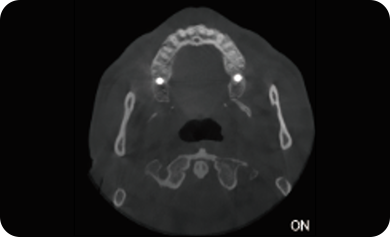

临床样片